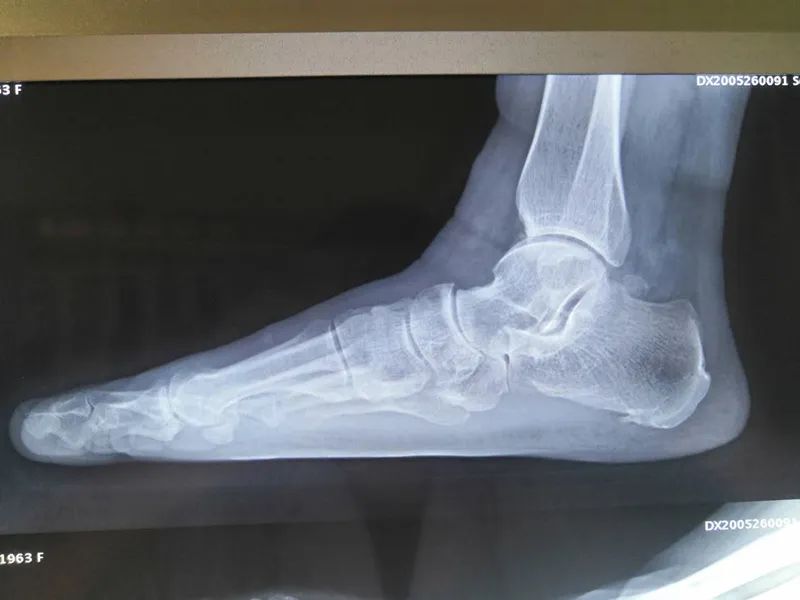

术前无明显足弓

经诊断,王女士患上了扁平足,这是一种以足内侧纵弓塌陷为主要表现的足部畸形。正常情况下,人的脚底是自然的弓形,但有扁平足的人,脚底基本是平的,没有明显的足弓,站立时脚底内侧会直接触地,这导致王女士足踝部多关节畸形病变、疼痛无法行走并丧失劳动能力。

51岁的王女士两年前走路出现右脚踝疼痛,近日,她明显感觉疼痛加重,甚至连短短500米的路程也无法走完,备受疾病困扰的她来到巴彦淖尔市医院手足显微外科治疗。